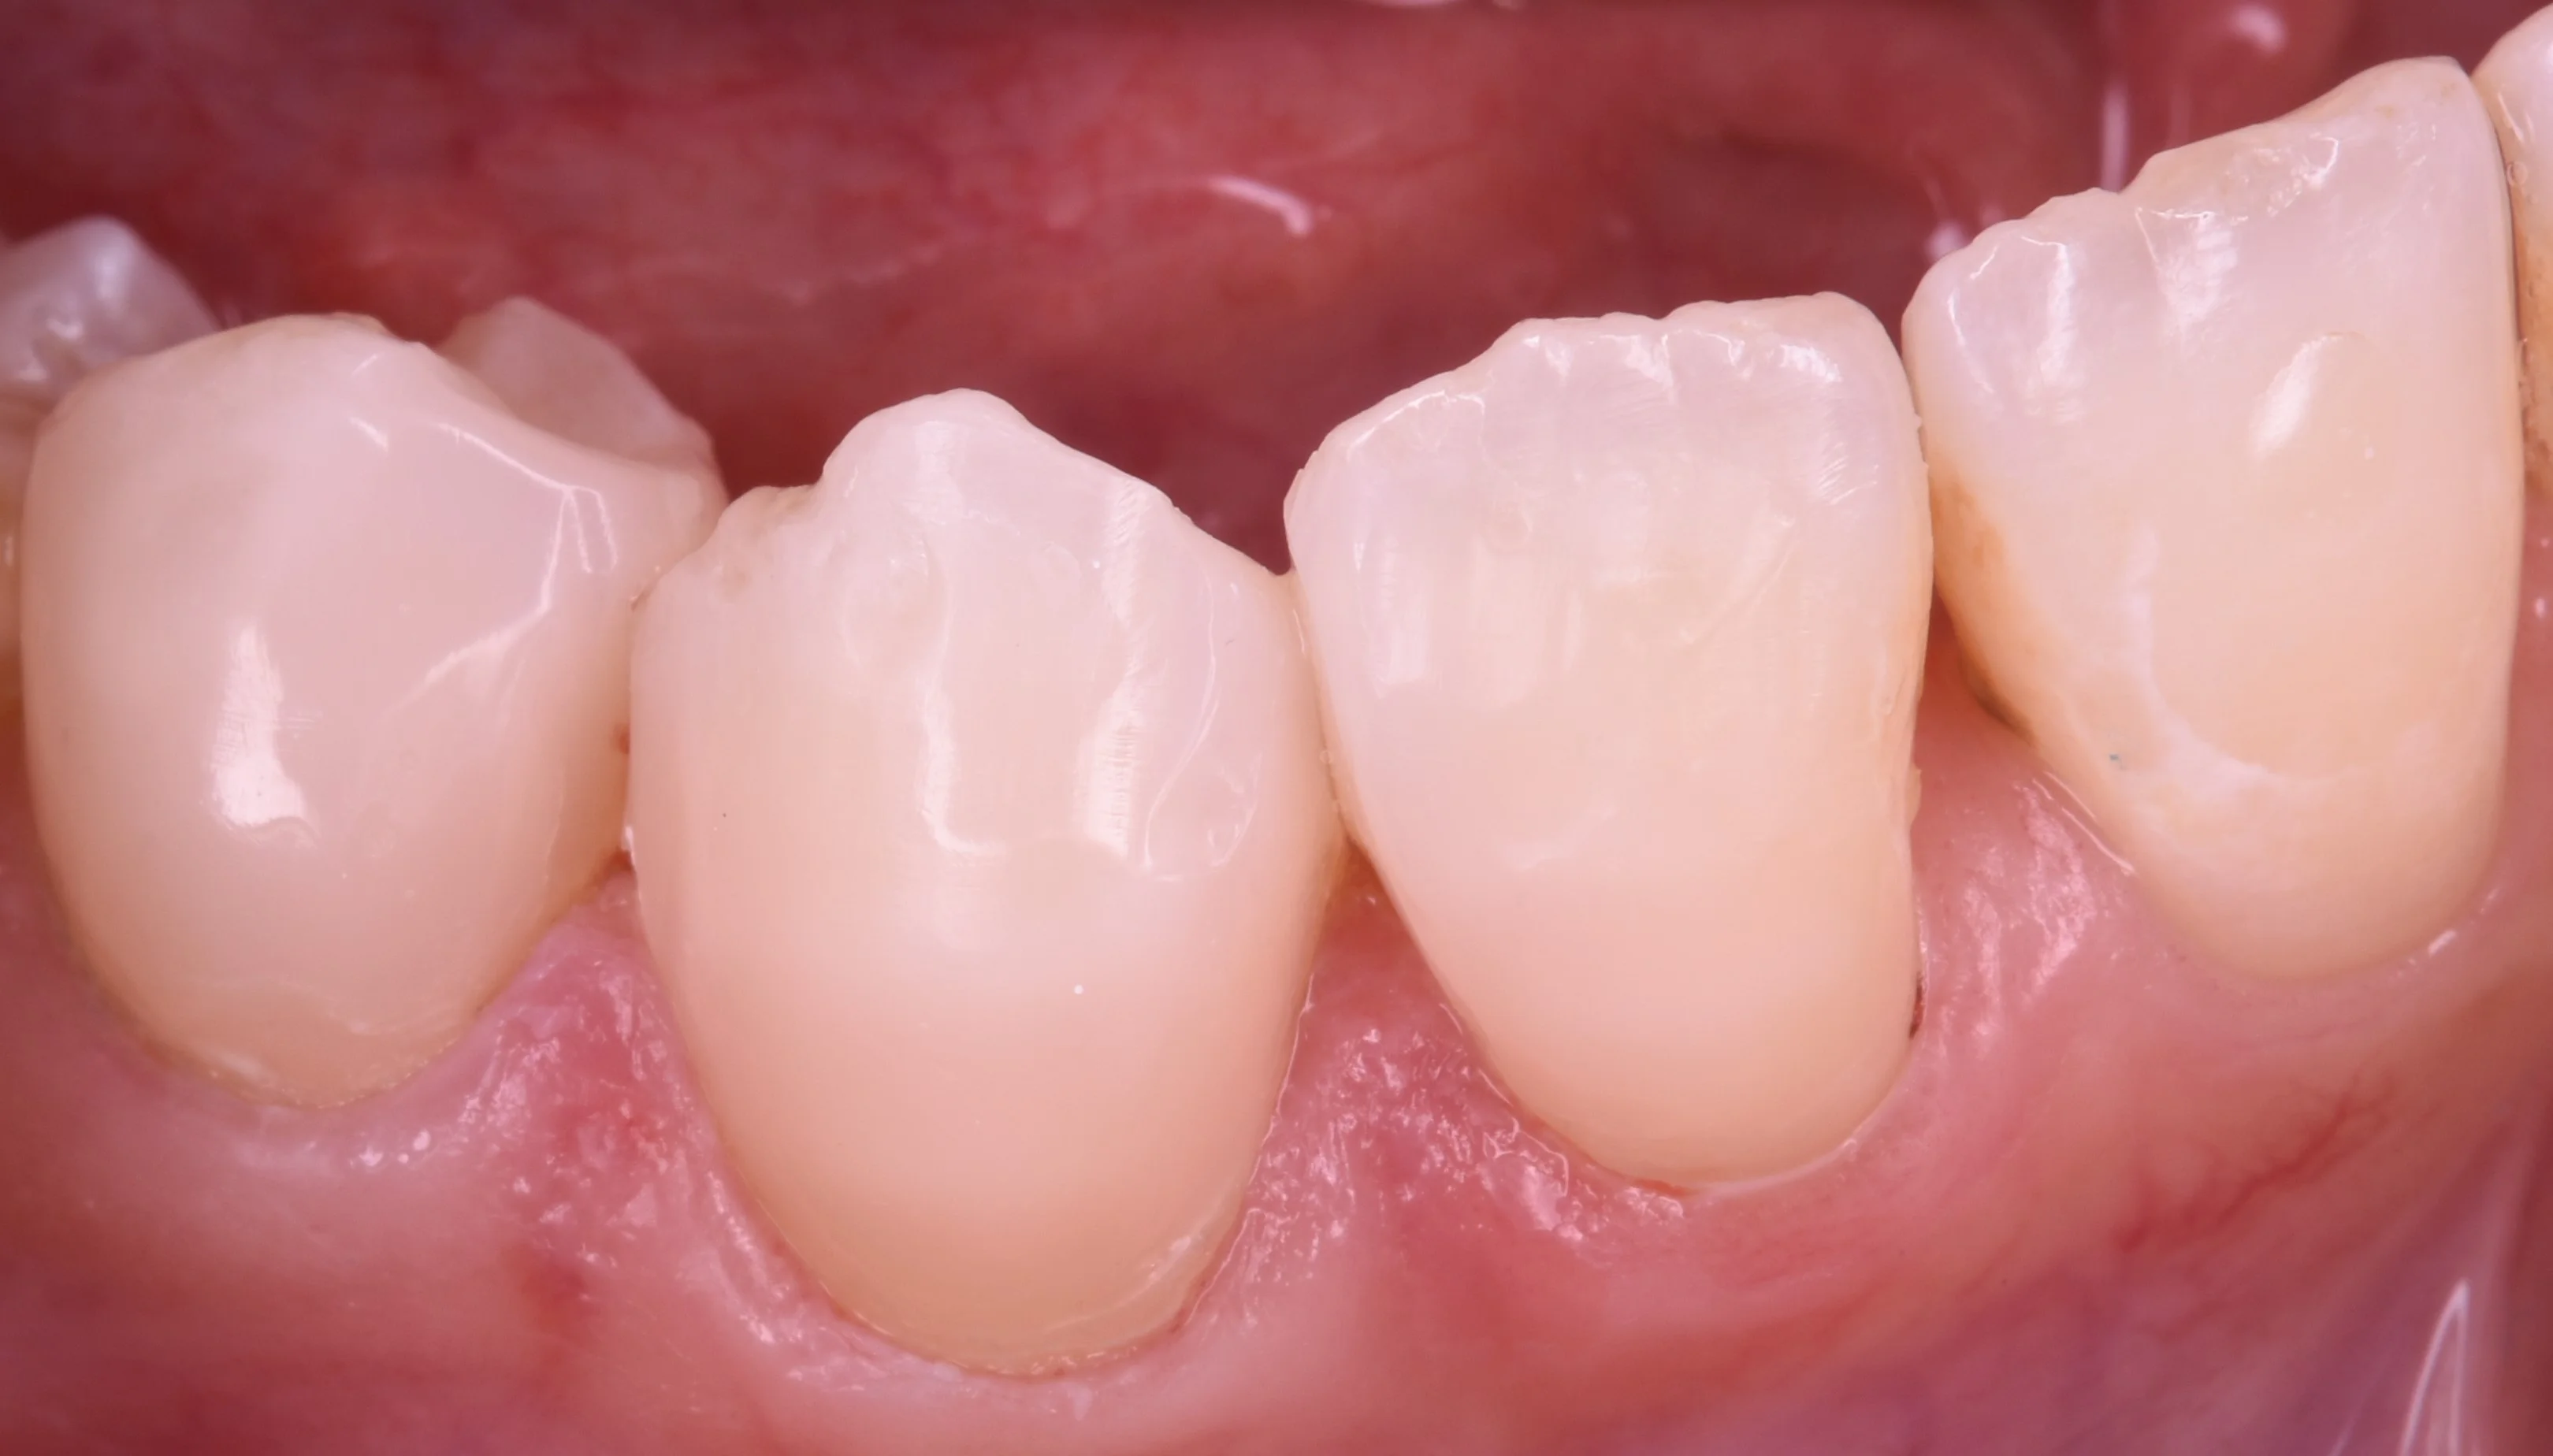

さて、虫歯を取り切った写真がこちらになります。

歯の本来の色が綺麗に出ました。

やはり相当健康な部分が少なくなっており、3本とも全体の歯の1/3近くなくなってしまっている状態でした。

先生によってはここまで歯がないと全周を削る被せ物を選択肢としていれる方が増えてくるかもしれません。

ですが、ダイレクトボンディングであれば・・・

こんな感じで可及的に歯を温存した上で、1日で治療を完了させることが可能ですヽ(゚∀゚)ノ パッ☆